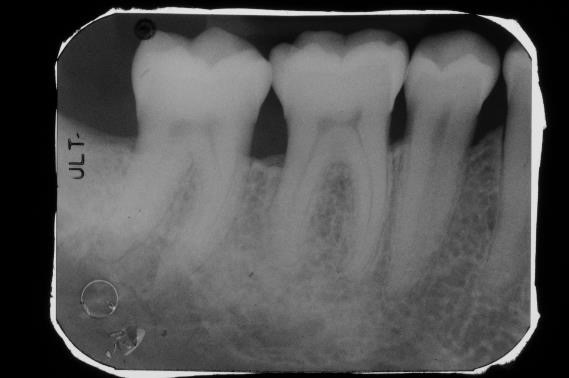

03/22 - Pre-operative radiograph. Deep intrabony defect visible on the distal aspect of tooth 46.

Deep intrabony defects treated using Straumann® Emdogain® - Dr. M. Stefanini